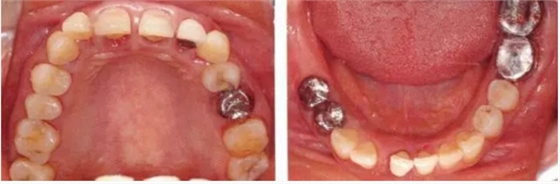

病例7

在正畸治療結(jié)束后仍然存在open contact的病例

▲圖15-1,2

在正畸??漆t(yī)生處接受了正畸治療,雖然上頜正畸治療已經(jīng)完成,但由于磨牙區(qū)的邊緣嵴不整齊而導(dǎo)致牙體之間存在空隙。要想在這個狀態(tài)下護(hù)理牙周組織以及咬合狀況是非常困難的。由此可見,在治療時,正畸??漆t(yī)生與全科口腔醫(yī)生保持目標(biāo)一致是非常重要的。